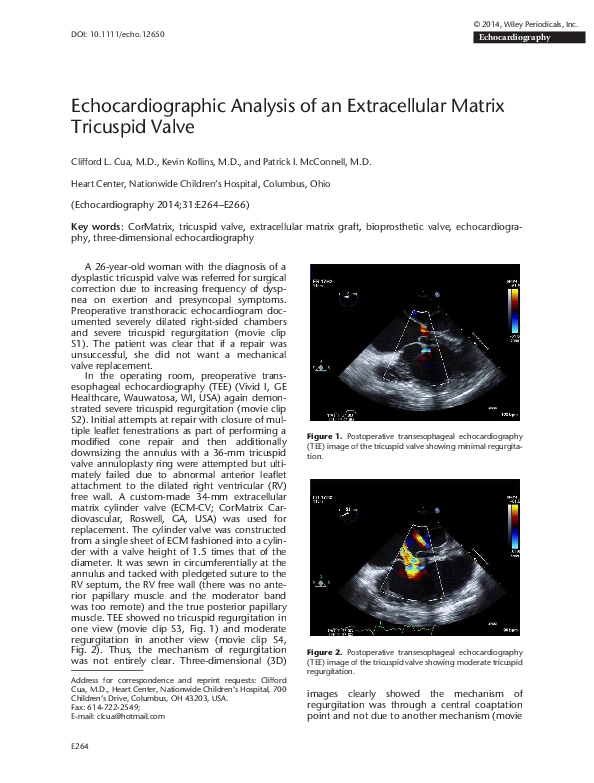

Two atrial baffle leaks (arrows) demonstrated by transesophageal